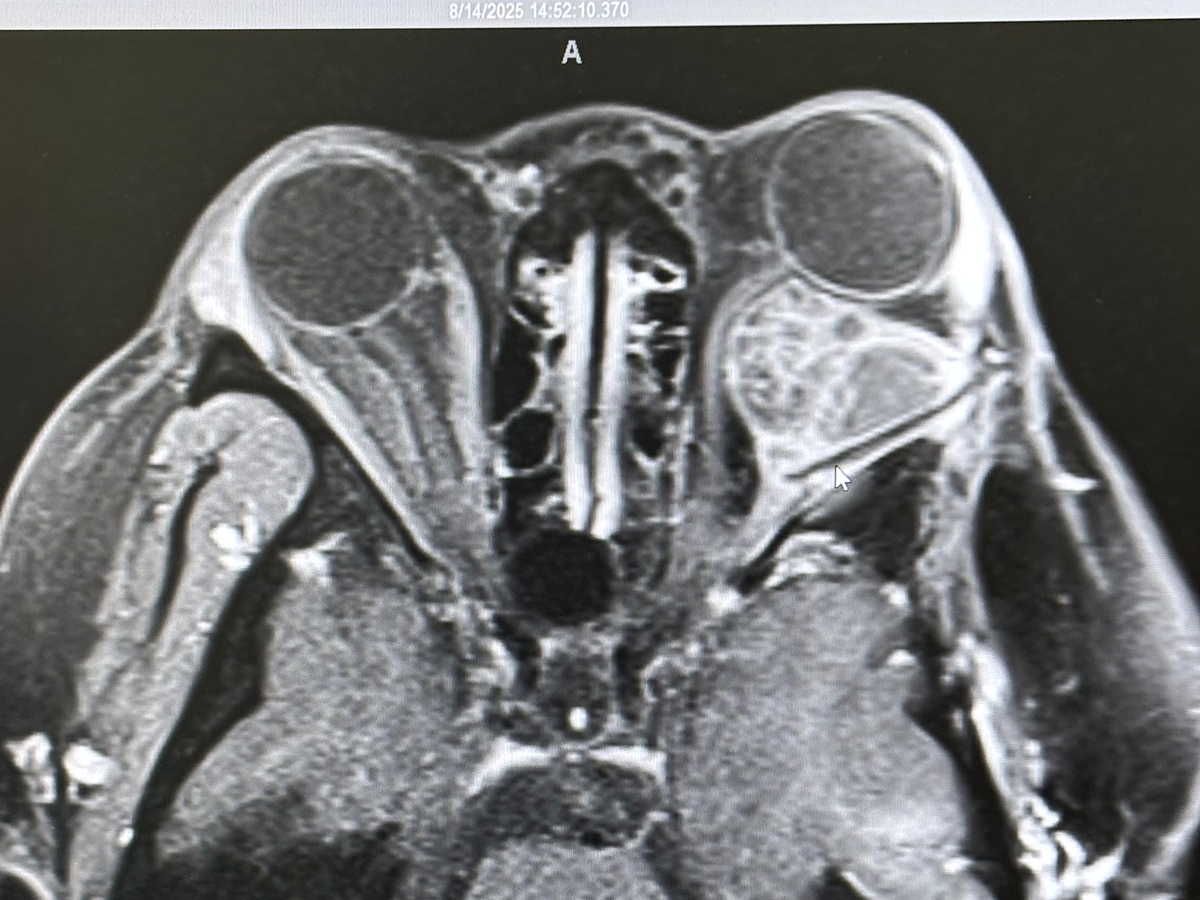

In Jan 2023 noticed I was having double vision very bad. After my monthly MRI my ENT Dr asked for more DNA testing on my tumor from 2022. They came back with the discovery of the BRAF V600E mutation. This time it was on the optic nerve of my left eye and this was why I was having double vision.

Eventually in Summer 2025 it was time to discuss what I had been avoiding for years EYE SURGERY I have done everything I can to avoid surgery on my "perfectly working eye" I look past the double vision (I still have a mild case), watery eye, light sensitivity (im not wearing sunnies in the club during my parties trying to be cool lmao i literally can not see!), the bulging (i don't even wear makeup anymore i hate it not even mascara or lashes), etc. The more I looked at my scans and how this thing is literally latched on to the nerve(s) attached directly to my eyeball I could lose my vision at any moment tbh ♀️ so possibly losing it because of the surgery is a risk I am willing to take to remove this thing and move on with my life.